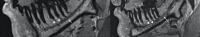

MRI is increasingly used as a diagnostic tool for visualising the dentoalveolar complex. A comprehensive review of the current indications and applications of MRI in the dental specialities of orthodontics (I), endodontics (II), prosthodontics (III), periodontics (IV), and oral surgery (V), pediatric dentistry (VI), operative dentistry is still missing and is therefore provided by the present work.The current literature on dental MRI shows that it is used for cephalometry in orthodontics and dentofacial orthopaedics, detection of dental pulp inflammation, characterisation of periapical and marginal periodontal pathologies of teeth, caries detection, and identification of the inferior alveolar nerve, impacted teeth and dentofacial anatomy for dental implant planning, respectively. Specific protocols regarding the miniature anatomy of the dentofacial complex, the presence of hard tissues, and foreign body restorations are used along with dedicated coils for the improved image quality of the facial skull.Dental MRI poses a clinically useful radiation-free imaging tool for visualising the dentoalveolar complex across dental specialities when respecting the indications and limitations.